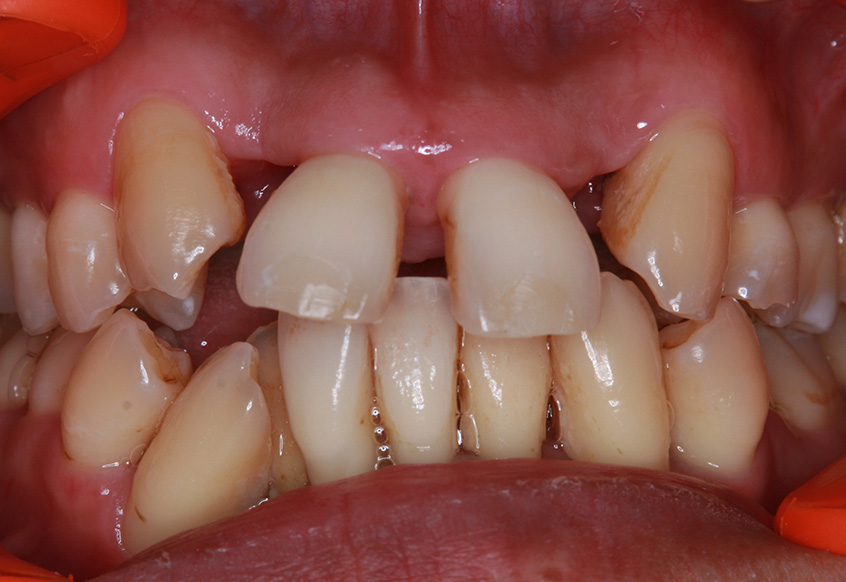

親知らずの痛みがなくなった患者さんは、昔から歯並びが気になっていることを打ち明けてくれました。特に上の歯が少し前に出ていたり、隙間があったりしている点を治したいそうです。そこで、まず上の歯並びの矯正治療を開始しました。

最初のお口の中 ワイヤー装着して治療を開始

| 主訴 | 上の前歯の歯並びを整えたい |

| 診断 | 歯列不正、う蝕歯 |

| 矯正装置 | 矯正ブラケットとワイヤー |

| 治療内容 | 上顎側切歯を2本抜歯した後、上顎の歯にブラケットを装着し、ワイヤー、矯正用ゴムで歯の移動を行いました。その後、被せ物の治療を行って治療を終了しています。 |